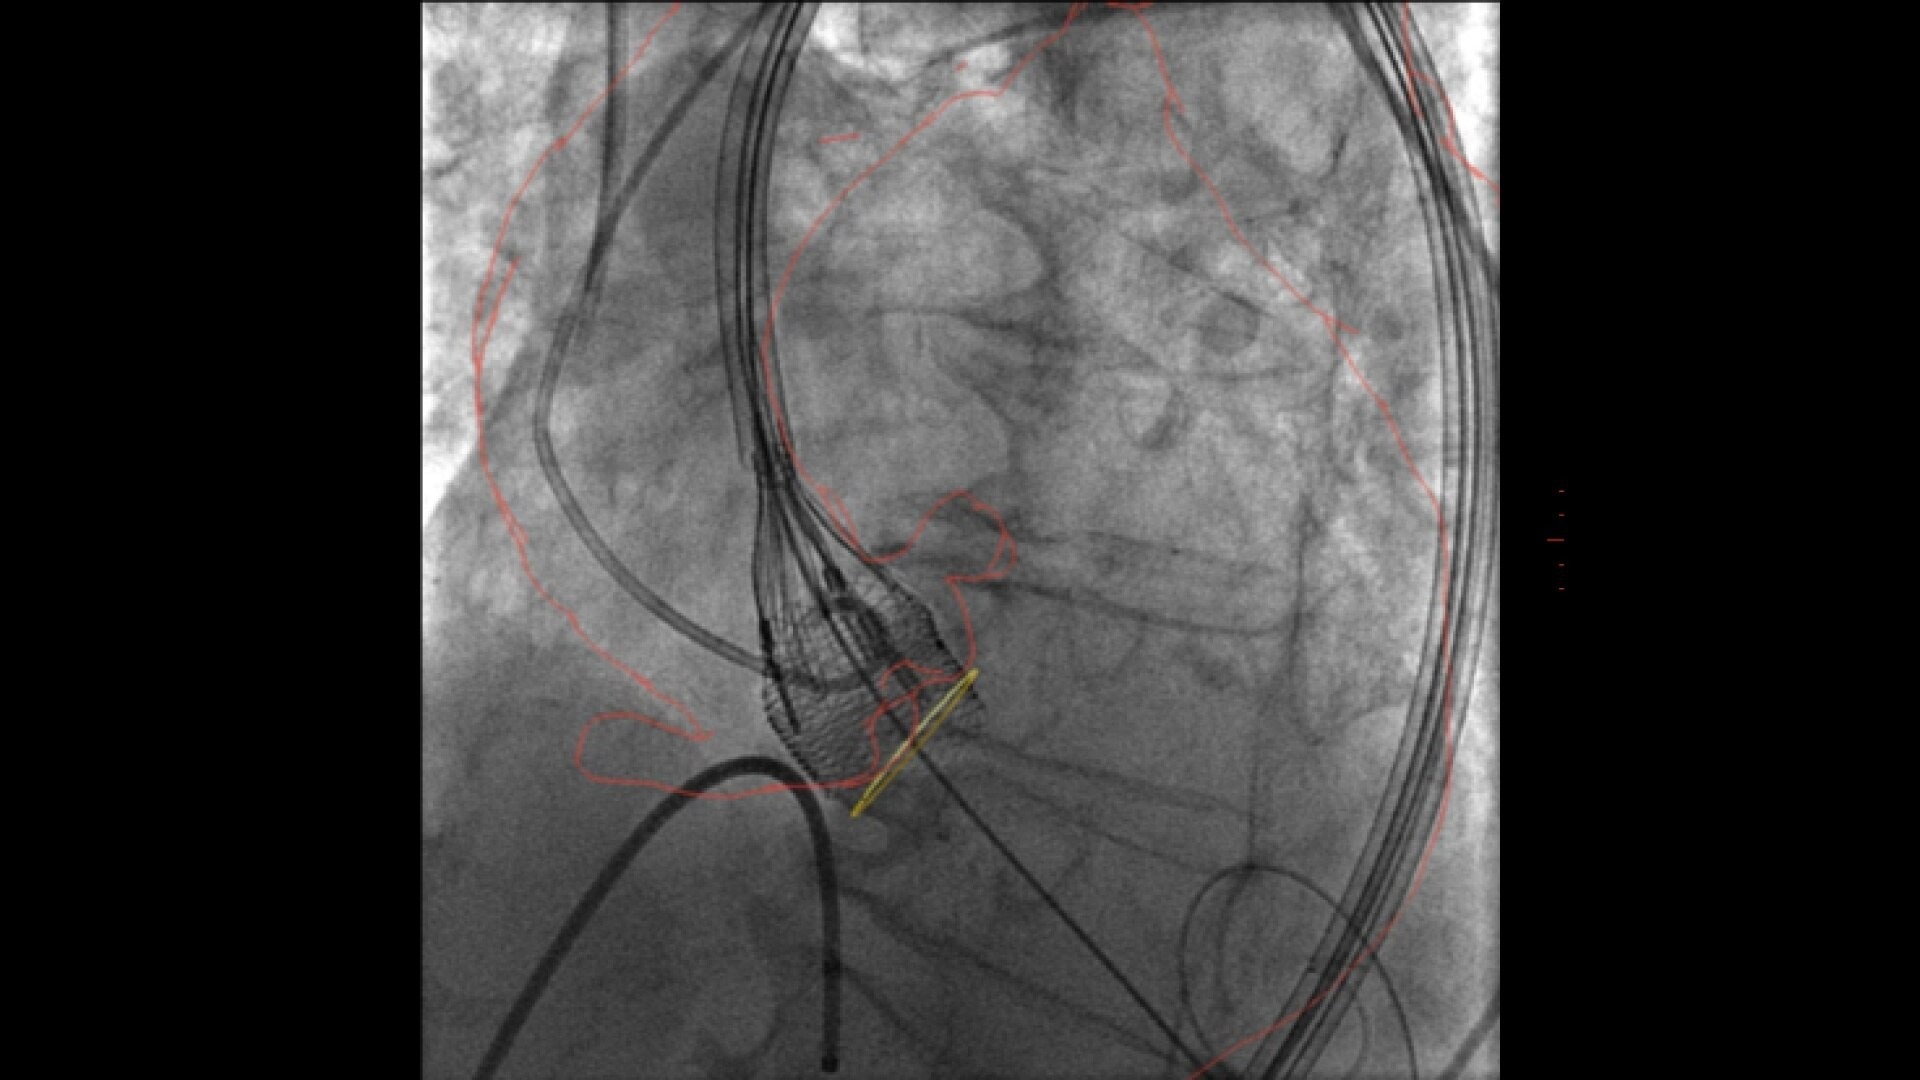

3D fusion guidance enhanced with Calcification Enhancement improves the visualization of moving contrasted structures.

Assess potential regurgitation with exceptional contrast visualization.

• 33% reduction in volume of contrast media²

• 33% reduction in X-ray dose³